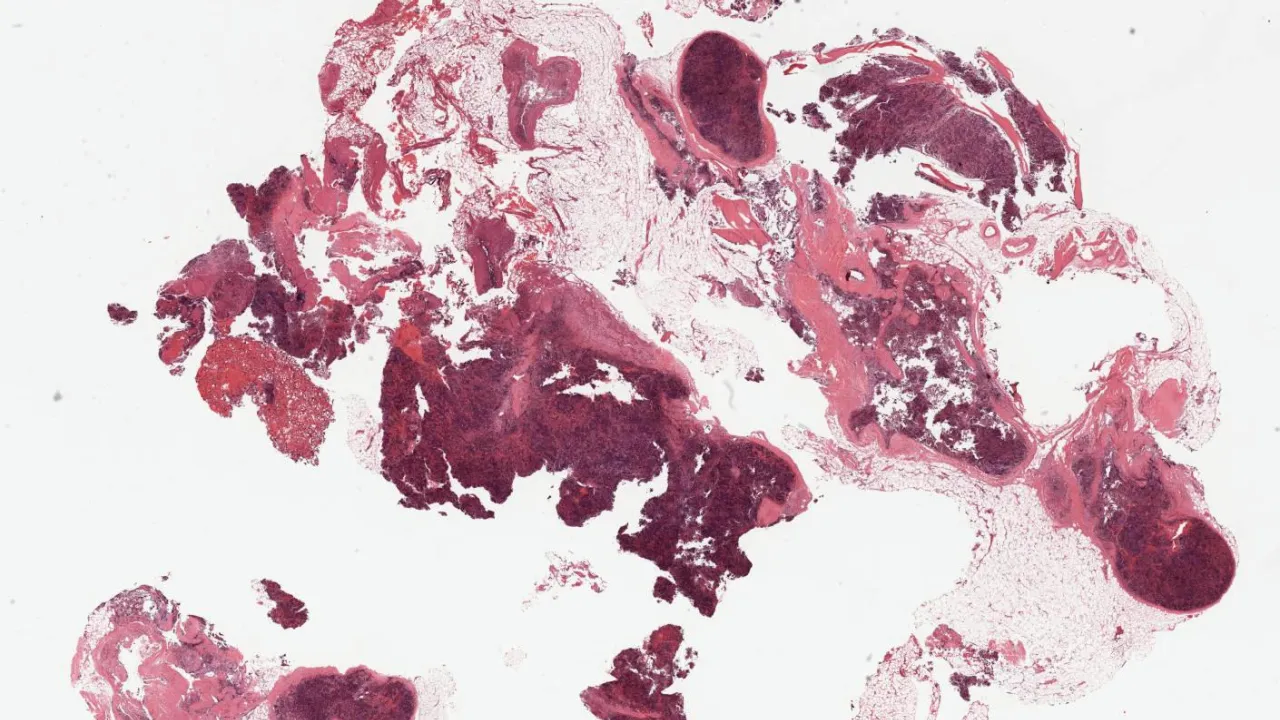

Soft Tissue, Extramedullary hematopoiesis